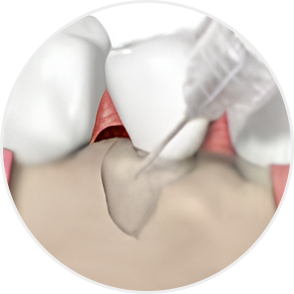

잇몸재생술에 사용되는 엠도게인(Emdogain)은

단순한 약이나 충전재가 아닙니다.

치아가 처음 만들어질 때 쓰이는 단백질 성분을 본떠 만든 특수한 젤입니다.

엠도게인은 치아와 잇몸이 처음 자라던 환경을 다시 만들어주는 역할을 합니다.

그 결과 손상된 잇몸뼈나 치주조직이 스스로 회복할 수 있도록 도와줍니다.

치조골 결손부 골이식술 효과

-

치주조직 깊숙이 작용하여 치아 뿌리 주변의 잇몸·치주인대·치조골 재생을 돕습니다.